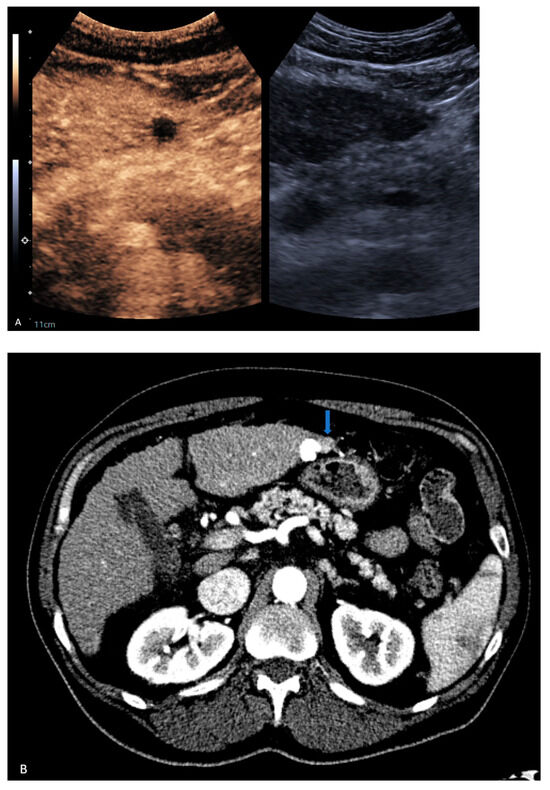

| 2 | CT | New | LR-5 | US did not identify new lesion |